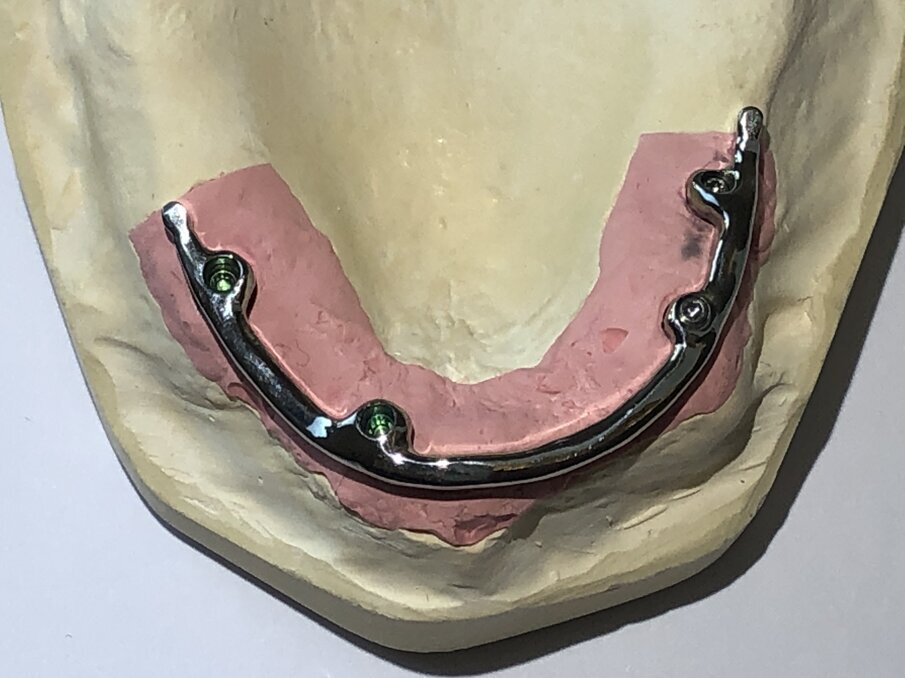

De foto’s van de dolderstaaf in deze publicatie zijn afkomstig van een patiënt, waarvan wij de constructie hebben vernieuwd wegens onvoldoende houvast. Om de dolderstaafconstructie eenvoudiger en sneller in de productie te vervaardigen, wordt vaak een nauwkeurig secundair onderdeel in de prothese achterwege gelaten. Dit betekent dat de huidige prothese zonder precisiebasis wordt geslepen en de dolderstaaf in de prothese wordt gepolymeriseerd zonder een geschikt secundair onderdeel (afbeelding 1, 2, 3, 4 en 5).

Een andere staafconstructie is de individueel handmatig gefreesde staafconstructie. Een identiek secundair deel van metaal is bevestigd in de prothese en verankerd met behulp van één of twee precisie-kunststoffen-onderdelen (afbeelding 8, 9 en 10, de groene delen).